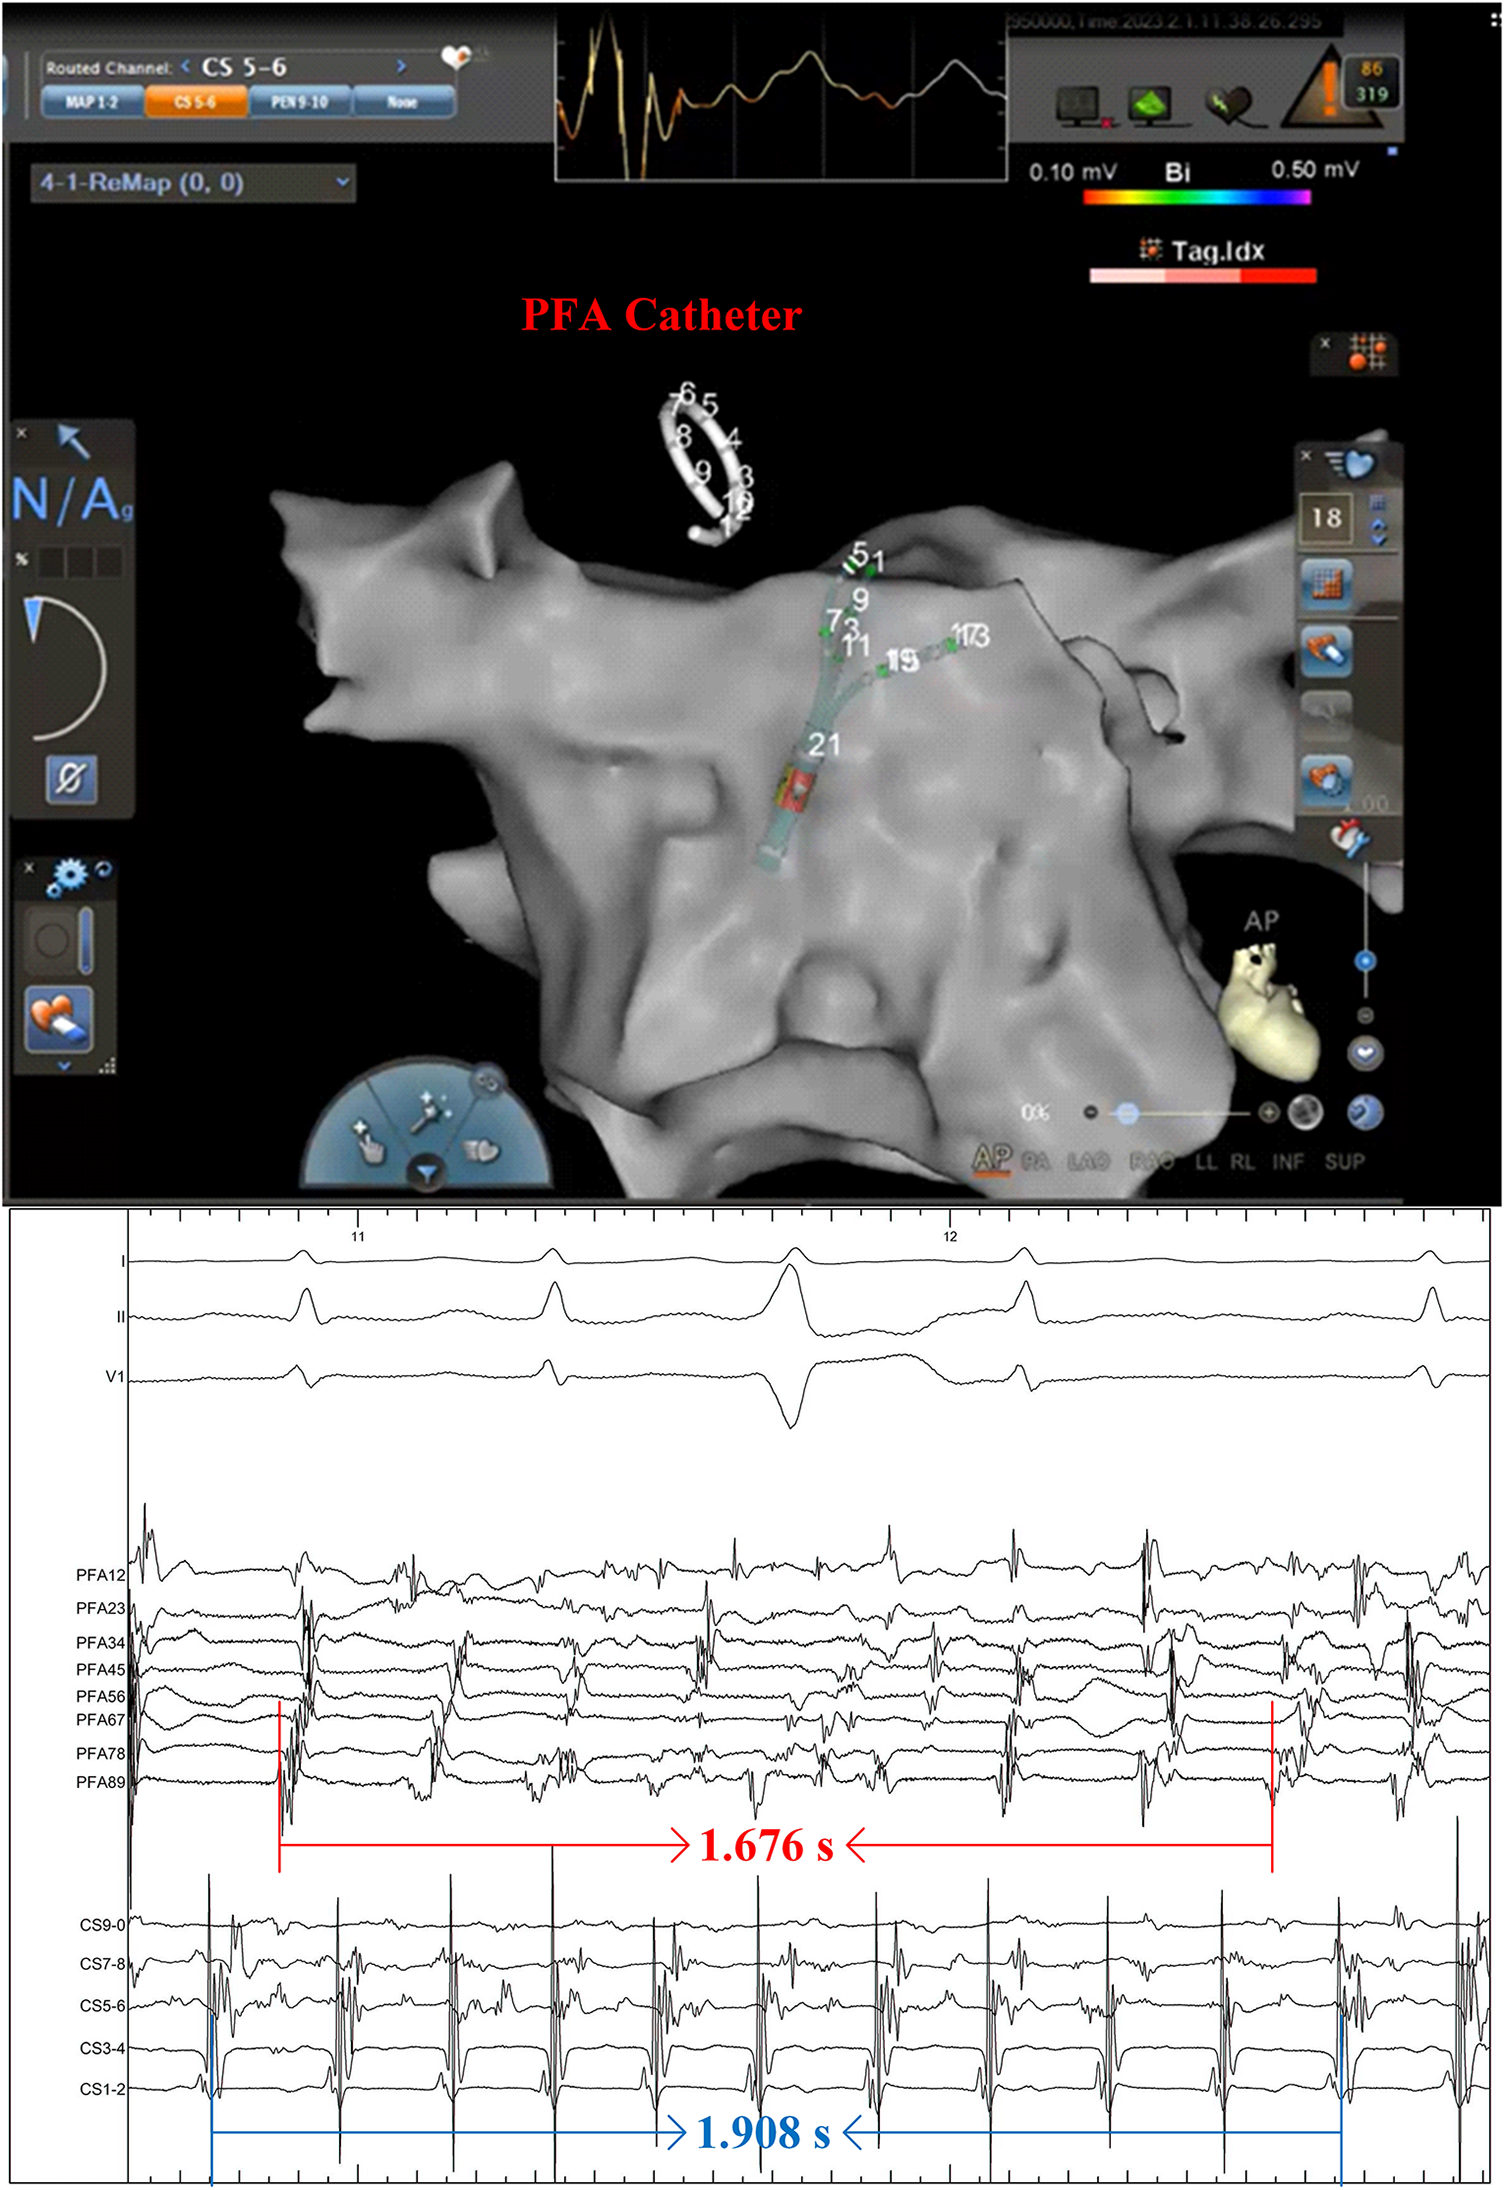

The patient presented sinus rhythm at the beginning of the procedure. However, atrial fibrillation recurred during left atrial mapping using a PentaRay catheter (Biosense Webster, Inc., Irvine, CA, USA). After all pulmonary veins were successfully isolated using an 8-F circular pulsed field ablation catheter (Shineyo Medical, Shanghai, China), atrial fibrillation persisted. The circular pulsed field ablation catheter was then placed within the superior vena cava, revealing some brief fractionated potentials and a local atrial fibrillation cycle length shorter than that in the coronary sinus (Figure 1). The atrial fibrillation terminated after a pulsed field ablation catheter discharge at the superior vena cava (biphasic, 1,400 V) (Figure 2). The left atrial voltage map pre- and post-pulsed field ablation is shown in Figure 3. The total procedure time was 2 h with a superior vena cava ablation time of 20 s.

Figure 1. A pulsed field ablation catheter was positioned within the superior vena cava, revealing the disorganized electrical activity. The intracardiac electrocardiogram was recorded at a speed of 100 mm/s.